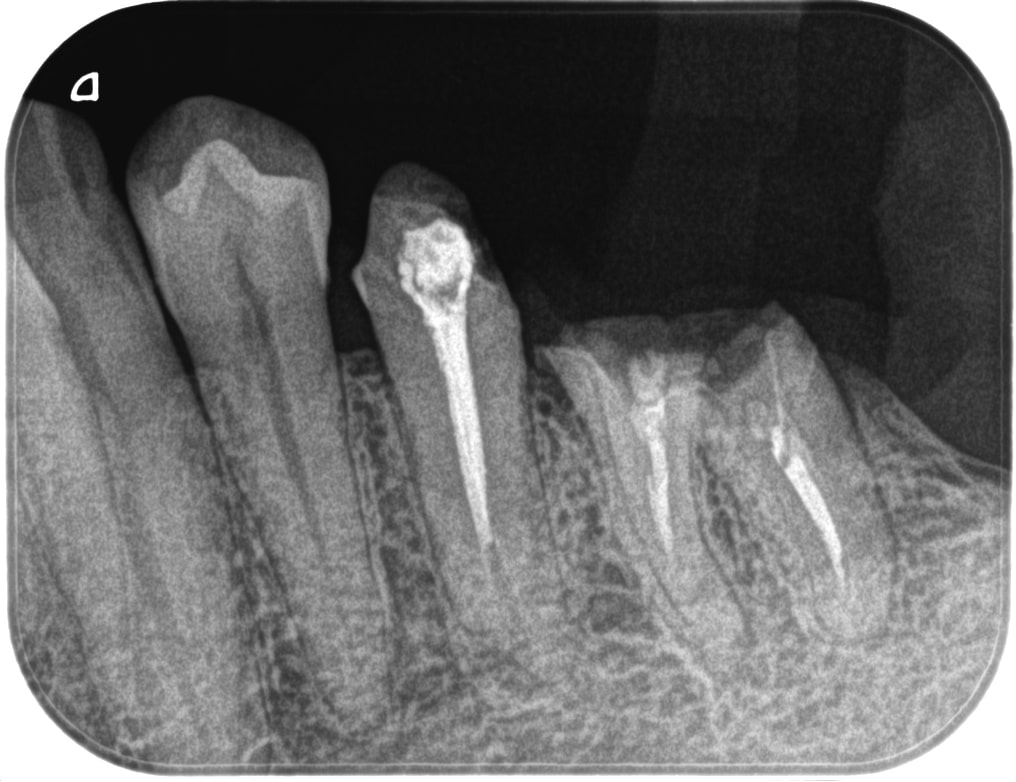

症例170代 男性 主訴 噛むと痛みがあり、しっかり噛めない

治療前

治療後

治療前

治療後

左下前・小臼歯部のブリッジによる荷重負担の為、隣在歯を守るインプラントを選択。

左下4番に単独インプラントを埋入。

オペ後、骨との密着値も良く、約2ヶ月後には、ジルコニアを装着し終了。

リスクとしては外科的侵襲がある。デメリットは、保険外診療の為、経済的負担がある。

費用 53万(税込)(オペ・仮歯・最終補綴物まで含む)